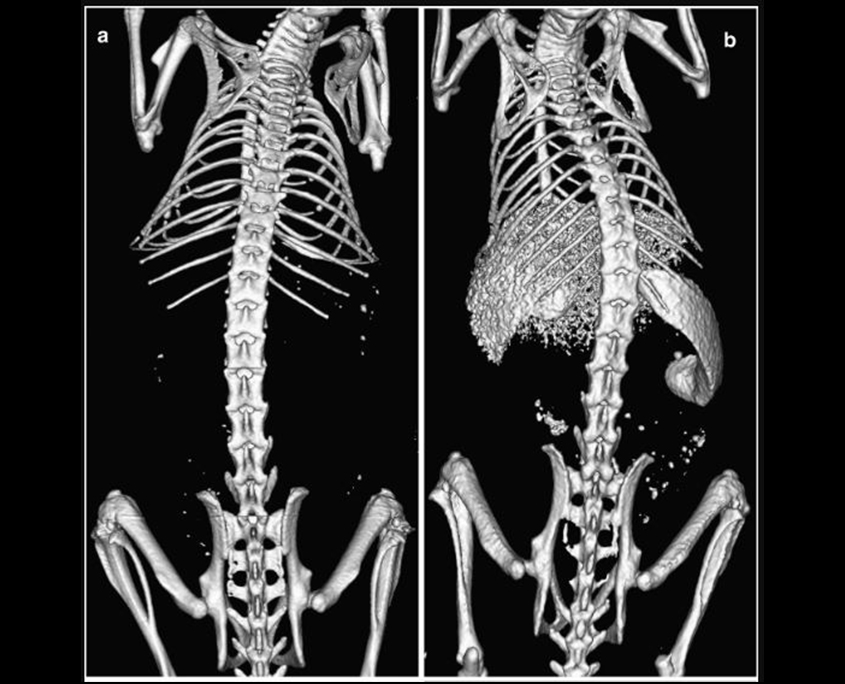

Organ Morphology Evaluation

Micro CT provides researchers with a non-invasive method for assessing organ morphology in small animal models. The 3D images generated by the system allow for a detailed evaluation of the structure and function of various organs, including the heart, liver, and lungs.

Micro CT is used to study the progression of various diseases and disorders in small animal models. The system’s ability to generate high-resolution, 3D images provides researchers with a comprehensive understanding of the effects of these diseases on the anatomy and function of the body.